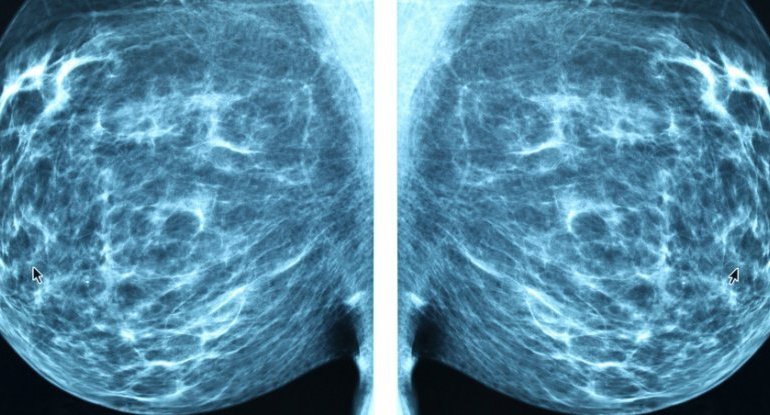

Ένα πρόγραμμα ηλεκτρονικών υπολογιστών μπορεί να εντοπίσει τον καρκίνο του μαστού από τις συνήθεις εξετάσεις με μεγαλύτερη ακρίβεια από τους γιατρούς, δήλωσαν οι ερευνητές και ελπίζουν ότι θα μπορούσε να αποδειχθεί μια σημαντική ανακάλυψη στον αγώνα κατά του καρκίνου.

Στη Βρετανία, γυναίκες άνω των 50 ετών συμβουλεύονται να κάνουν μαστογραφία κάθε τρία χρόνια, τα αποτελέσματα των οποίων αναλύονται από δύο ανεξάρτητους εμπειρογνώμονες.

Αλλά η ερμηνεία των σαρώσεων αφήνει περιθώρια σφαλμάτων. Ένα μικρό ποσοστό όλων των μαστογραφιών είναι ψευδώς θετικό (διαγιγνώσκεται η ασθένεια χωρίς να υπάρχει) ή ψευδώς αρνητικό (υπάρχει η ασθένεια αλλά αποτυγχάνει η διάγνωση).